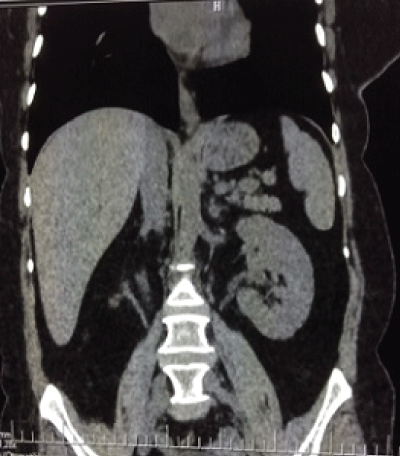

A 49-year- old woman was admitted to emergency service with acute urinary retention due to an obstructed urethral stone. After relieving retention with the insertion of urethral catheter, direct kidney urether and bladder (KUB) x-ray and urinary ultrasonography (USG) were performed. KUB x-ray revealed multiple opacities at right lower quadrant of minor pelvis (Figure 1). Her medical history revealed that she had experience recurrent square shaped urinary stone pass and hadn't had any urological intervention. Ultrasonography demonstrated a right side terminal ureteral cystic dilatation, containing multiple stones and atrophic duplex systems (Renal bipolar length: 5cm, renal parenchymal thicknesses 0, 5cm, and dilatation of the lower system pole). For further investigation a non-contrast tomography showed right terminal ureteral dilatation (3×2×2cm), multiple calculus in 1×1cm size and duplex system anomaly (Figure 1-3).